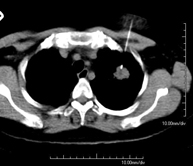

- PAAF (Punción) Tórax guiada por TC Prueba que consiste en obtener una muestra de tejido de lesiones torácicas, como por ejemplo masas pulmonares, mediastínicas, lesiones óseas, etc. Para ello se administra anestesia local sobre la zona de la punción, la cual se realiza con agujas de fino calibre. Todo el procedimiento se realiza controlado por imágenes obtenidas por Tomografía Computarizada (TC) en varios momentos de la punción, mediante un equipo de Fluoroscopia-TC. Tras la prueba, el paciente permanece unas horas hospitalizado. Es necesario aportar pruebas de coagulación antes de la punción. Prueba que consiste en obtener una muestra de tejido de lesiones torácicas, como por ejemplo masas pulmonares, mediastínicas, lesiones óseas, etc. Para ello se administra anestesia local sobre la zona de la punción, la cual se realiza con agujas de fino calibre. Todo el procedimiento se realiza controlado por imágenes obtenidas por Tomografía Computarizada (TC) en varios momentos de la punción, mediante un equipo de Fluoroscopia-TC. Tras la prueba, el paciente permanece unas horas hospitalizado. Es necesario aportar pruebas de coagulación antes de la punción.

- Biopsia tórax guiada por TC Consiste en obtener una muestra de tejido de una determinada lesión torácica, como por ejemplo del pulmón, del mediastino, del esternón, etc. A veces se realiza bajo sedación, con la ayuda del equipo de anestesia. Se utilizan agujas que permiten la obtención de un cilindro de la lesión a estudiar, que se enviará a Anatomía Patológica para su análisis histológico. Todo el procedimiento se realiza controlado con imágenes obtenidas por Tomografía Computarizada (TC) en varios momentos de la biopsia, mediante un equipo de Fluoroscopia-TC. Tras la prueba, el paciente permanece hospitalizado para controlar su evolución. Es necesario aportar pruebas de coagulación antes de la punción. Consiste en obtener una muestra de tejido de una determinada lesión torácica, como por ejemplo del pulmón, del mediastino, del esternón, etc. A veces se realiza bajo sedación, con la ayuda del equipo de anestesia. Se utilizan agujas que permiten la obtención de un cilindro de la lesión a estudiar, que se enviará a Anatomía Patológica para su análisis histológico. Todo el procedimiento se realiza controlado con imágenes obtenidas por Tomografía Computarizada (TC) en varios momentos de la biopsia, mediante un equipo de Fluoroscopia-TC. Tras la prueba, el paciente permanece hospitalizado para controlar su evolución. Es necesario aportar pruebas de coagulación antes de la punción.